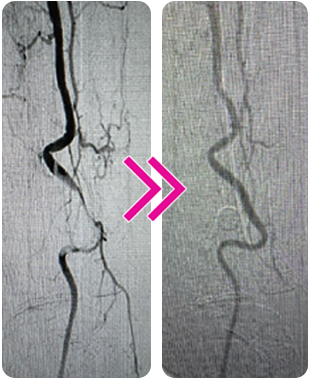

Successful Removal of Organized Thrombus With the Pounce™ Thrombectomy System After Failed Pharmacomechanical Treatment

Vince Weaver, MD

A 53-year-old man presented with 2-week onset of rest pain. Noninvasive studies suggested occlusive thrombus disease throughout the SFA and popliteal artery. The initial angiogram confirmed organized thrombus throughout the SFA and popliteal arteries.